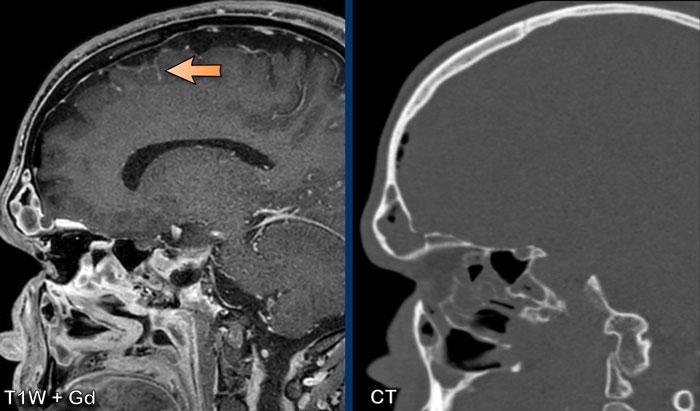

Các hình ảnh này của một bệnh nhân nam 58 tuổi nhập viện với triệu chứng đau đầu ở tư thế ngồi và đứng.

Hình ảnh

Có ngấm thuốc màng cứng đều đặn ở cả khoang trên lều và dưới lều.

Lưu ý các não thất nhỏ.

Tiếp tục với các hình ảnh mặt phẳng đứng dọc…

Hình 1

Các dấu hiệu khá tinh tế, nhưng bao gồm:

- Sa thấp trung não với giảm khoảng cách cầu-vú, xóa bể trên hố yên, dẹt phần trước cầu não và gập góc thân não tại chỗ nối sọ-cổ.

- Vùng dưới đồi gập qua mặt lưng hố yên, tuyến yên hơi phì đại (vòng tròn trắng).

- Liên hợp đồi thị bị hạ thấp; phần sau thể chai bị hạ thấp (dấu hiệu “dương vật rũ”). Lưu ý sự dẹt của bể trên tiểu não.

- Trong trường hợp này, amygdale ở vị trí bình thường và không có thoát vị (vòng tròn vàng).

Kết luận: các dấu hiệu điển hình của hạ áp lực nội sọ.

Hình 2

Sau điều trị bằng miếng vá máu ngoài màng cứng không định vị mục tiêu, não và thân não đã trở về vị trí bình thường với sự bình thường hóa cấu hình các bể và não thất IV.